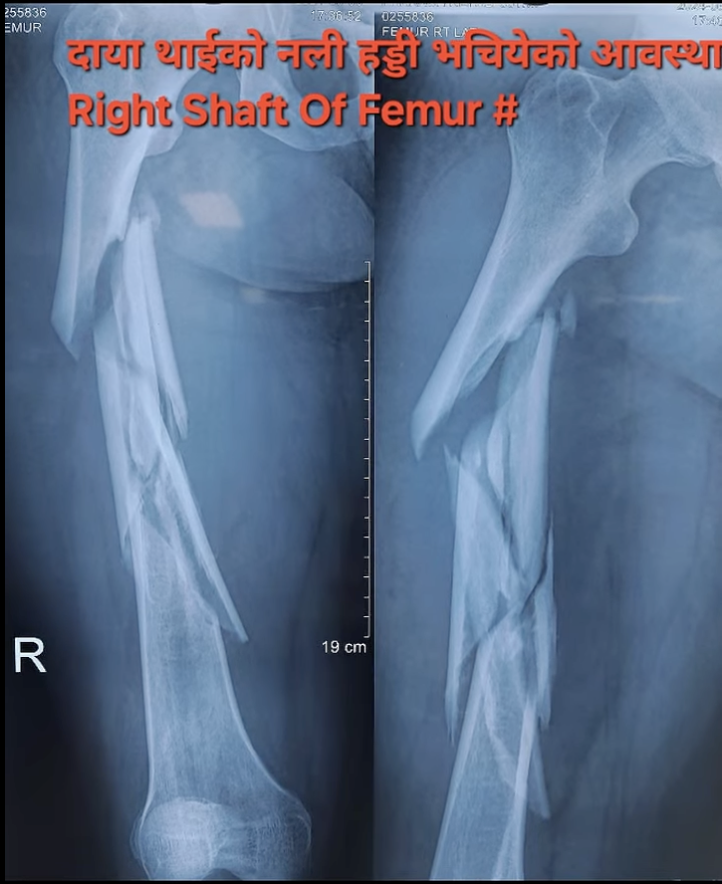

थाईको हड्डी (Femur Shaft) भाँचिएको केस: बाइक दुर्घटनापछि सफल शल्यक्रिया

बाइक दुर्घटनापछि आएको थाईको हड्डी भाँचिएको केस, Intramedullary Interlocking Nail प्रयोग गरी सफल उपचार।